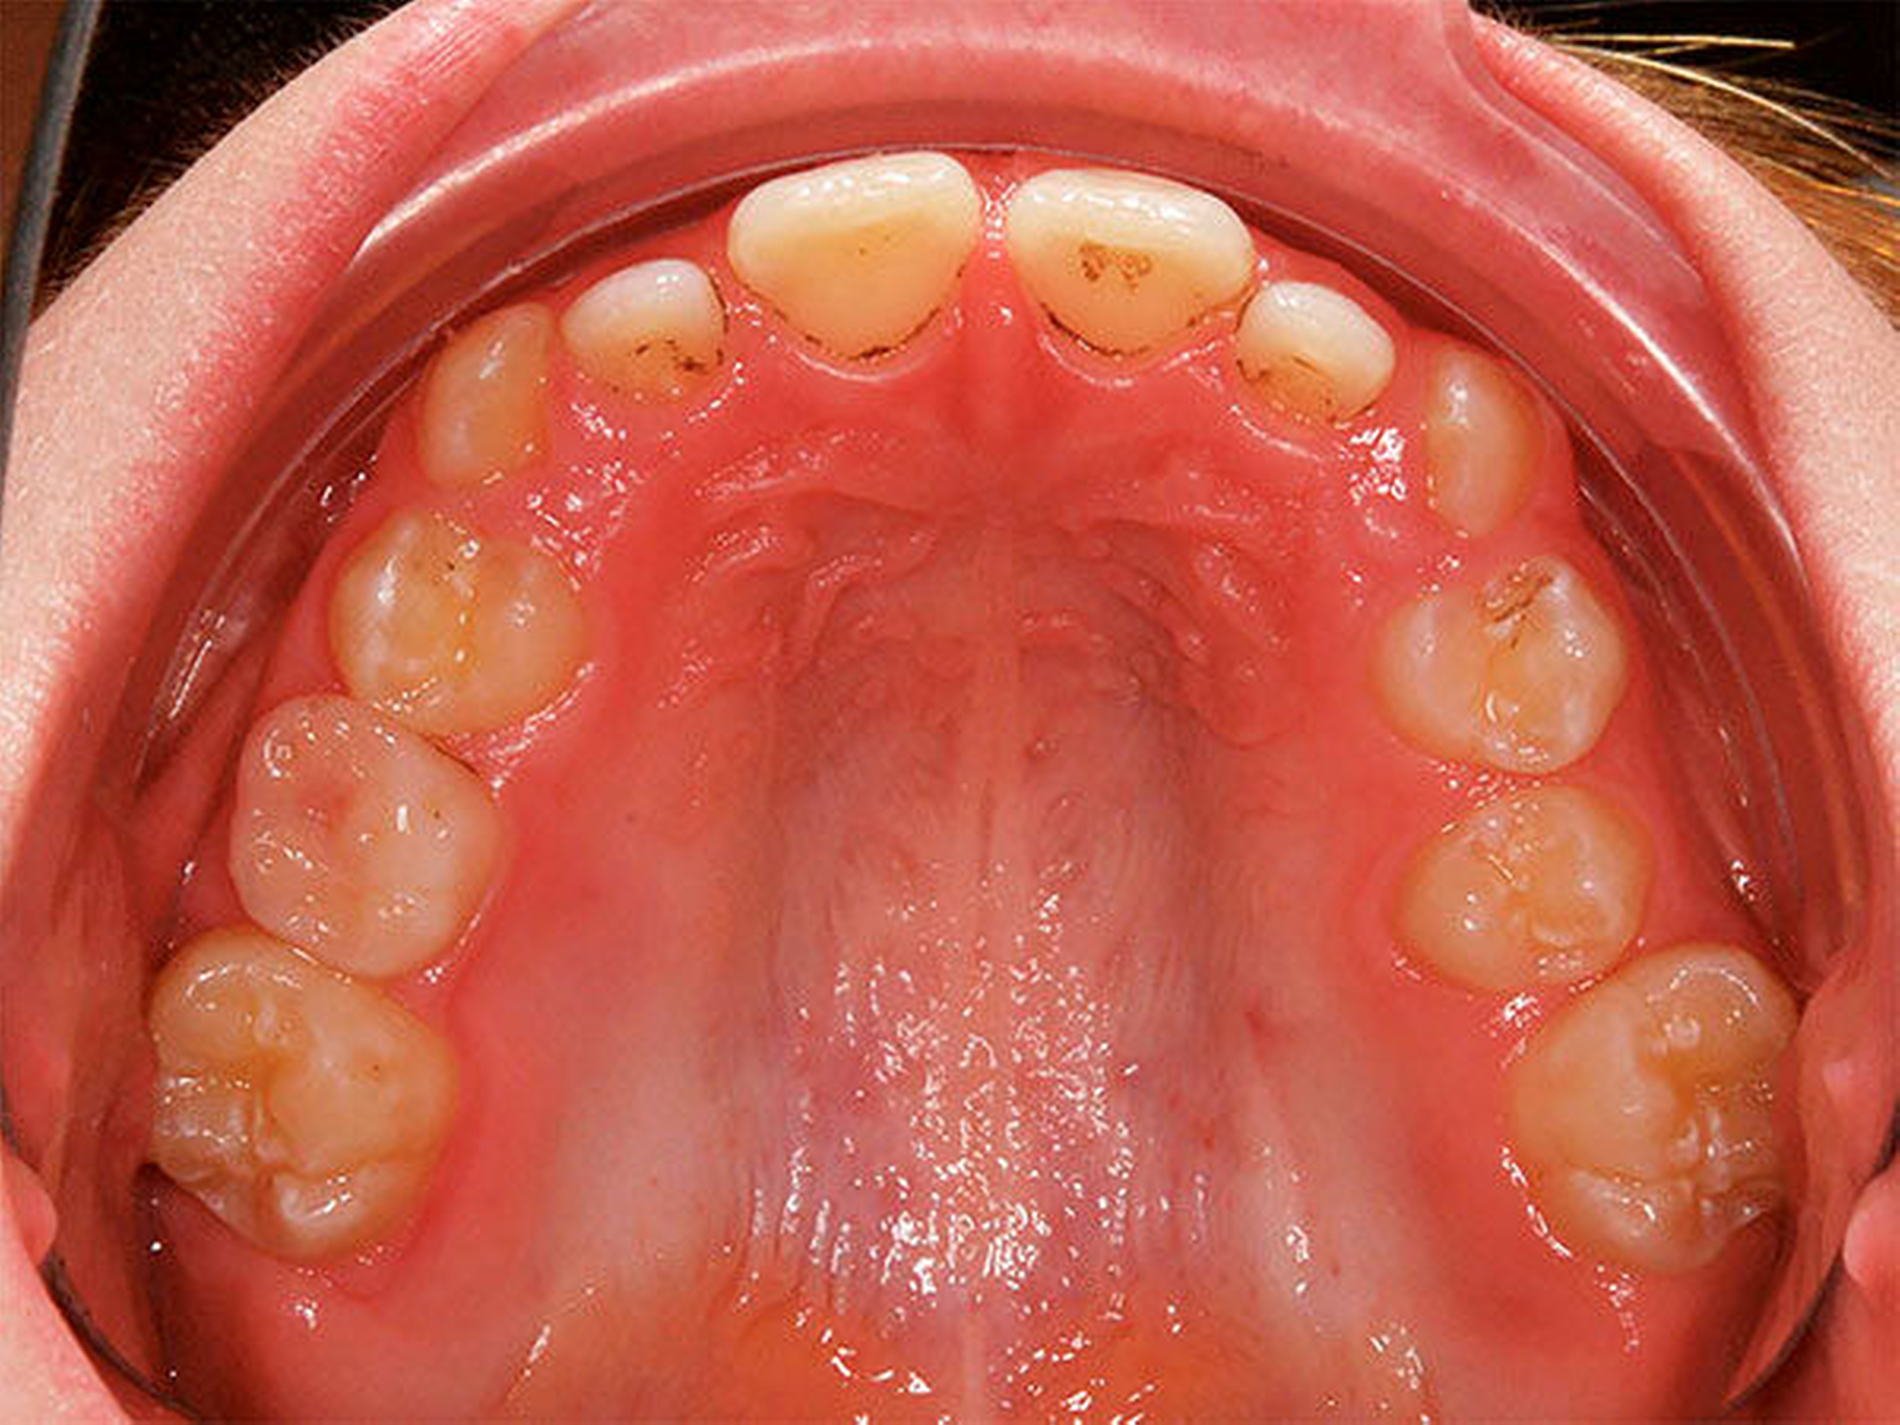

In der Gruppe des progenen Formenkreises werden Zahn- und Kieferfehlstellungen unterschiedlichster Ätiologie zusammengefasst. Diese können durch ein Missverhältnis im Wachstum beider Kiefer bedingt sein, das heißt durch Überentwicklung (Makro-/Prognathie) des Unterkiefers und/oder Unterentwicklung (Mikro-/Retrognathie) des Oberkiefers [Rakosi, 1989]. Besteht ein frontaler Kreuzbiss von Einzelzähnen oder einer ganzen Zahngruppe wird der Oberkiefer durch den Unterkiefer „eingefangen“, das heißt durch die palatinalwärts positionierten OK-Inzisiven wird das Oberkieferwachstum im Alveolarfortsatzbereich gehemmt sowie das Unterkieferwachstum „freigegeben“, da der Unterkiefer sich postnatal in sagittaler Richtung ohnehin stärker als der Oberkiefer entwickelt [Lux, 2004]. Zudem kann eine Zwangsbissführung des Unterkiefers nach ventral vorliegen [Keeling, 1998]. Diese kann zusätzlich zu einer unerwünschten Wachstumsstimulation des Unterkiefers mit nachfolgender skelettaler Manifestation führen. Mit einem therapeutisch eingestellten sicheren frontalen Überbiss (sagittal und vertikal) kann die weitere Kieferentwicklung koordinierter ablaufen (Abbildung 4). Die Anomalien des progenen Formenkreises besitzen häufig auch eine hereditäre Komponente, wobei unphysiologische Ruheweichteilbeziehungen oder Dysfunktionen den Phänotyp deutlich verstärken können. Da bei Klasse-III-Dysgnathien die skelettalen Therapieergebnisse bei frühzeitigem Behandlungsbeginn am besten sind, sollte frühzeitig mit einer kausalen Therapie begonnen werden – also sobald eine ausreichende Compliance des Patienten es zulässt, [Baccetti, 1998; Da Silva, 1998; Franci, 2004; Lang, 2001; Saadi, 2000].